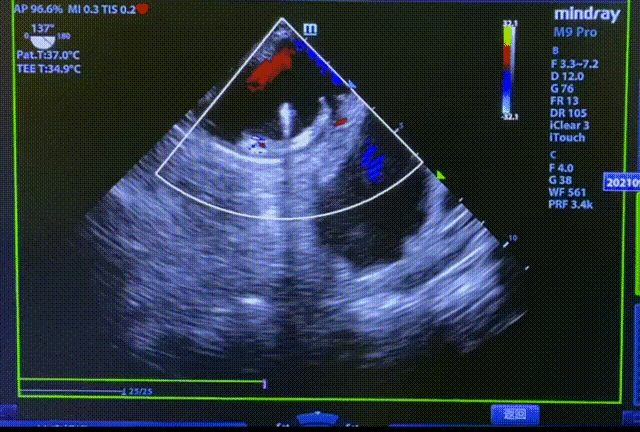

心脏彩超显示,左心房前后径36mm, 左心室舒张末期前后径48 mm,EF 62%,提示左房增大,二尖瓣可见微量反流。

常规肝位造影显示,左心耳锚定区约26mm, 开口约29mm, 因此选择型号为LT-LAA-2834的LAmbre™左心耳封堵器对患者实施封堵。LAmbre™植入过程一步到位,U型钩均完全展开。随后复查造影及TEE结果,封堵盘呈“碗状”形态完美贴合于左心耳口部,无残余分流,牵拉测试稳定,综合评估符合COST原则,随后完美释放,封堵效果理想。术后,患者各项指标正常,身体恢复良好。

释放后TEE检查(135°)